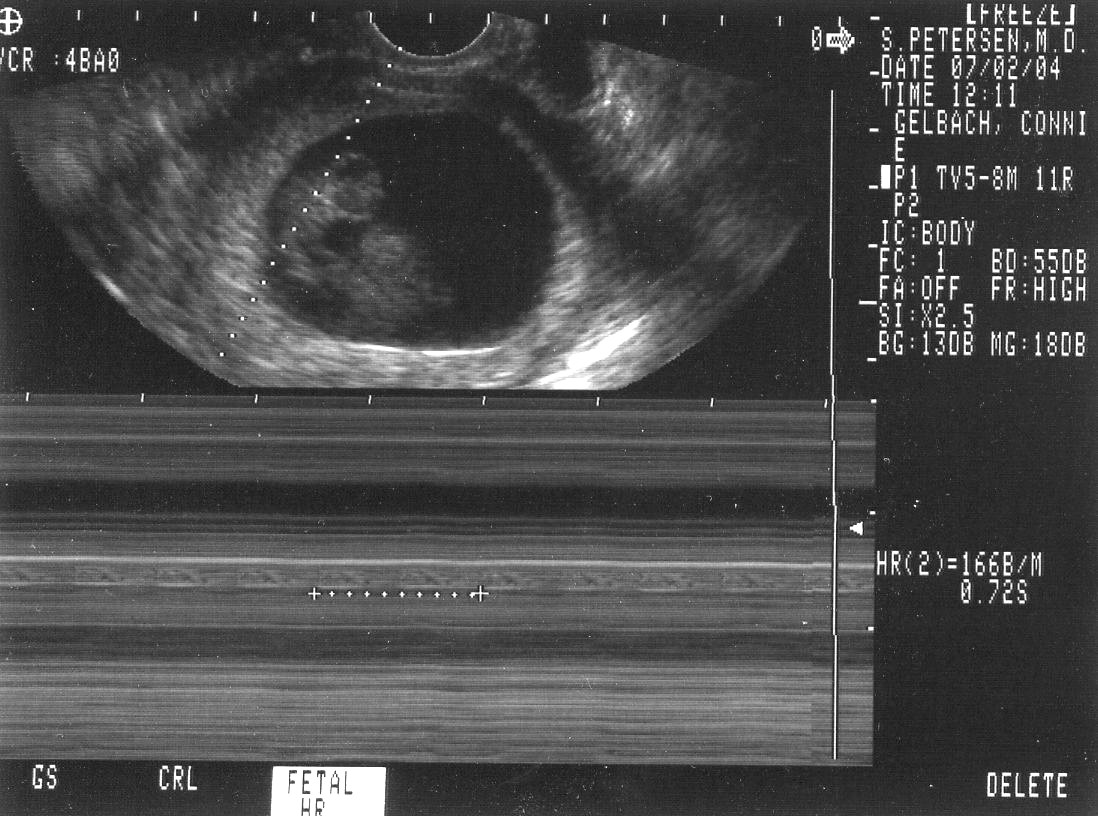

Sonograms